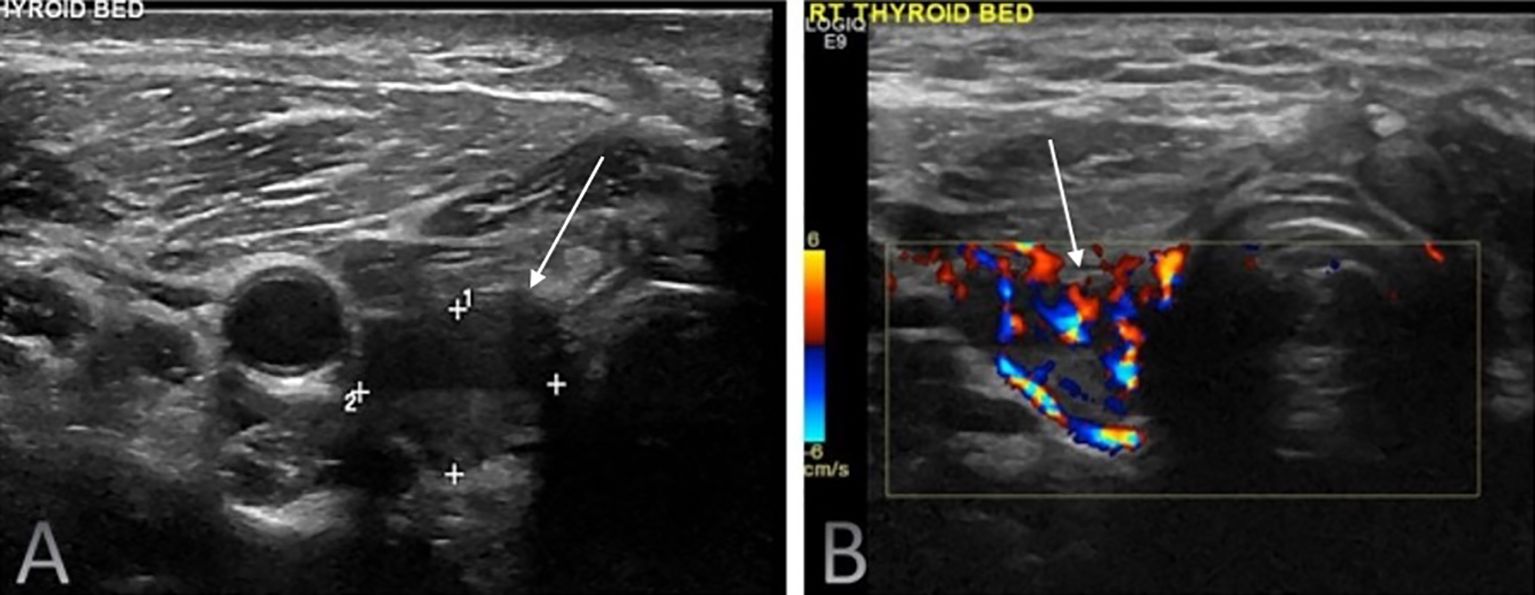

Background: Differentiated thyroid cancer (DTC; including papillary and follicular thyroid cancers) has favourable survival outcomes, with related mortality below 10%. However, 20–30% of patients experience recurrence. Surveillance primarily relies on neck ultrasonography (US) and serum thyroglobulin (Tg) assessment. Purpose: This study evaluated the diagnostic performance of neck US in detecting locoregional recurrence following total thyroidectomy and compared its effectiveness with serum Tg. Materials and Methods: This retrospective, single-centre study analysed 941 DTC patients who underwent total thyroidectomy and neck US between 2009 and 2019. Suspicious US findings were correlated with serum Tg levels and anti-thyroglobulin antibody status. Disease persistence (<6 months) /recurrence (>6 months) was confirmed via fine-needle aspiration cytology/biopsy, iodine scintigraphy, CT, or PET-CT. Patients without US-detected lesions were assessed clinically, biochemically, and via follow-up US. Results: Neck US had a sensitivity of 98.9%, specificity of 63.1%, positive predictive value (PPV) of 50.7%, negative predictive value (NPV) of 99.3%, and an accuracy of 73.01%. Serum Tg (cutoff 1.8 ng/ml derived from receiver operating characteristic analysis) had a sensitivity of 69.2%, specificity of 91.8%, PPV of 61.4%, NPV of 94.1%, and an accuracy of 88.28%. Among 149 patients with US-detected lesions and Tg <1.8 ng/ml, 22 (14.8%) had locoregional recurrence. Five of 43 patients with Tg <0.1 ng/ml had confirmed recurrence. Among lymph nodes ≤6 mm in short-axis diameter with an indistinct fatty hilum, 69.6% were benign. Persistence was detected in 38.5% of patients within six months post-treatment, whereas most true recurrences (61.5%) manifested after six months. Conclusion: Neck US is highly sensitive but moderately specific for detecting locoregional recurrence post-thyroidectomy, complementing Tg. Study limitations include its retrospective design, single-centre setting, and lack of inter-observer variability assessment. A risk-adapted multimodal surveillance strategy with 6-monthly US for two years is recommended.